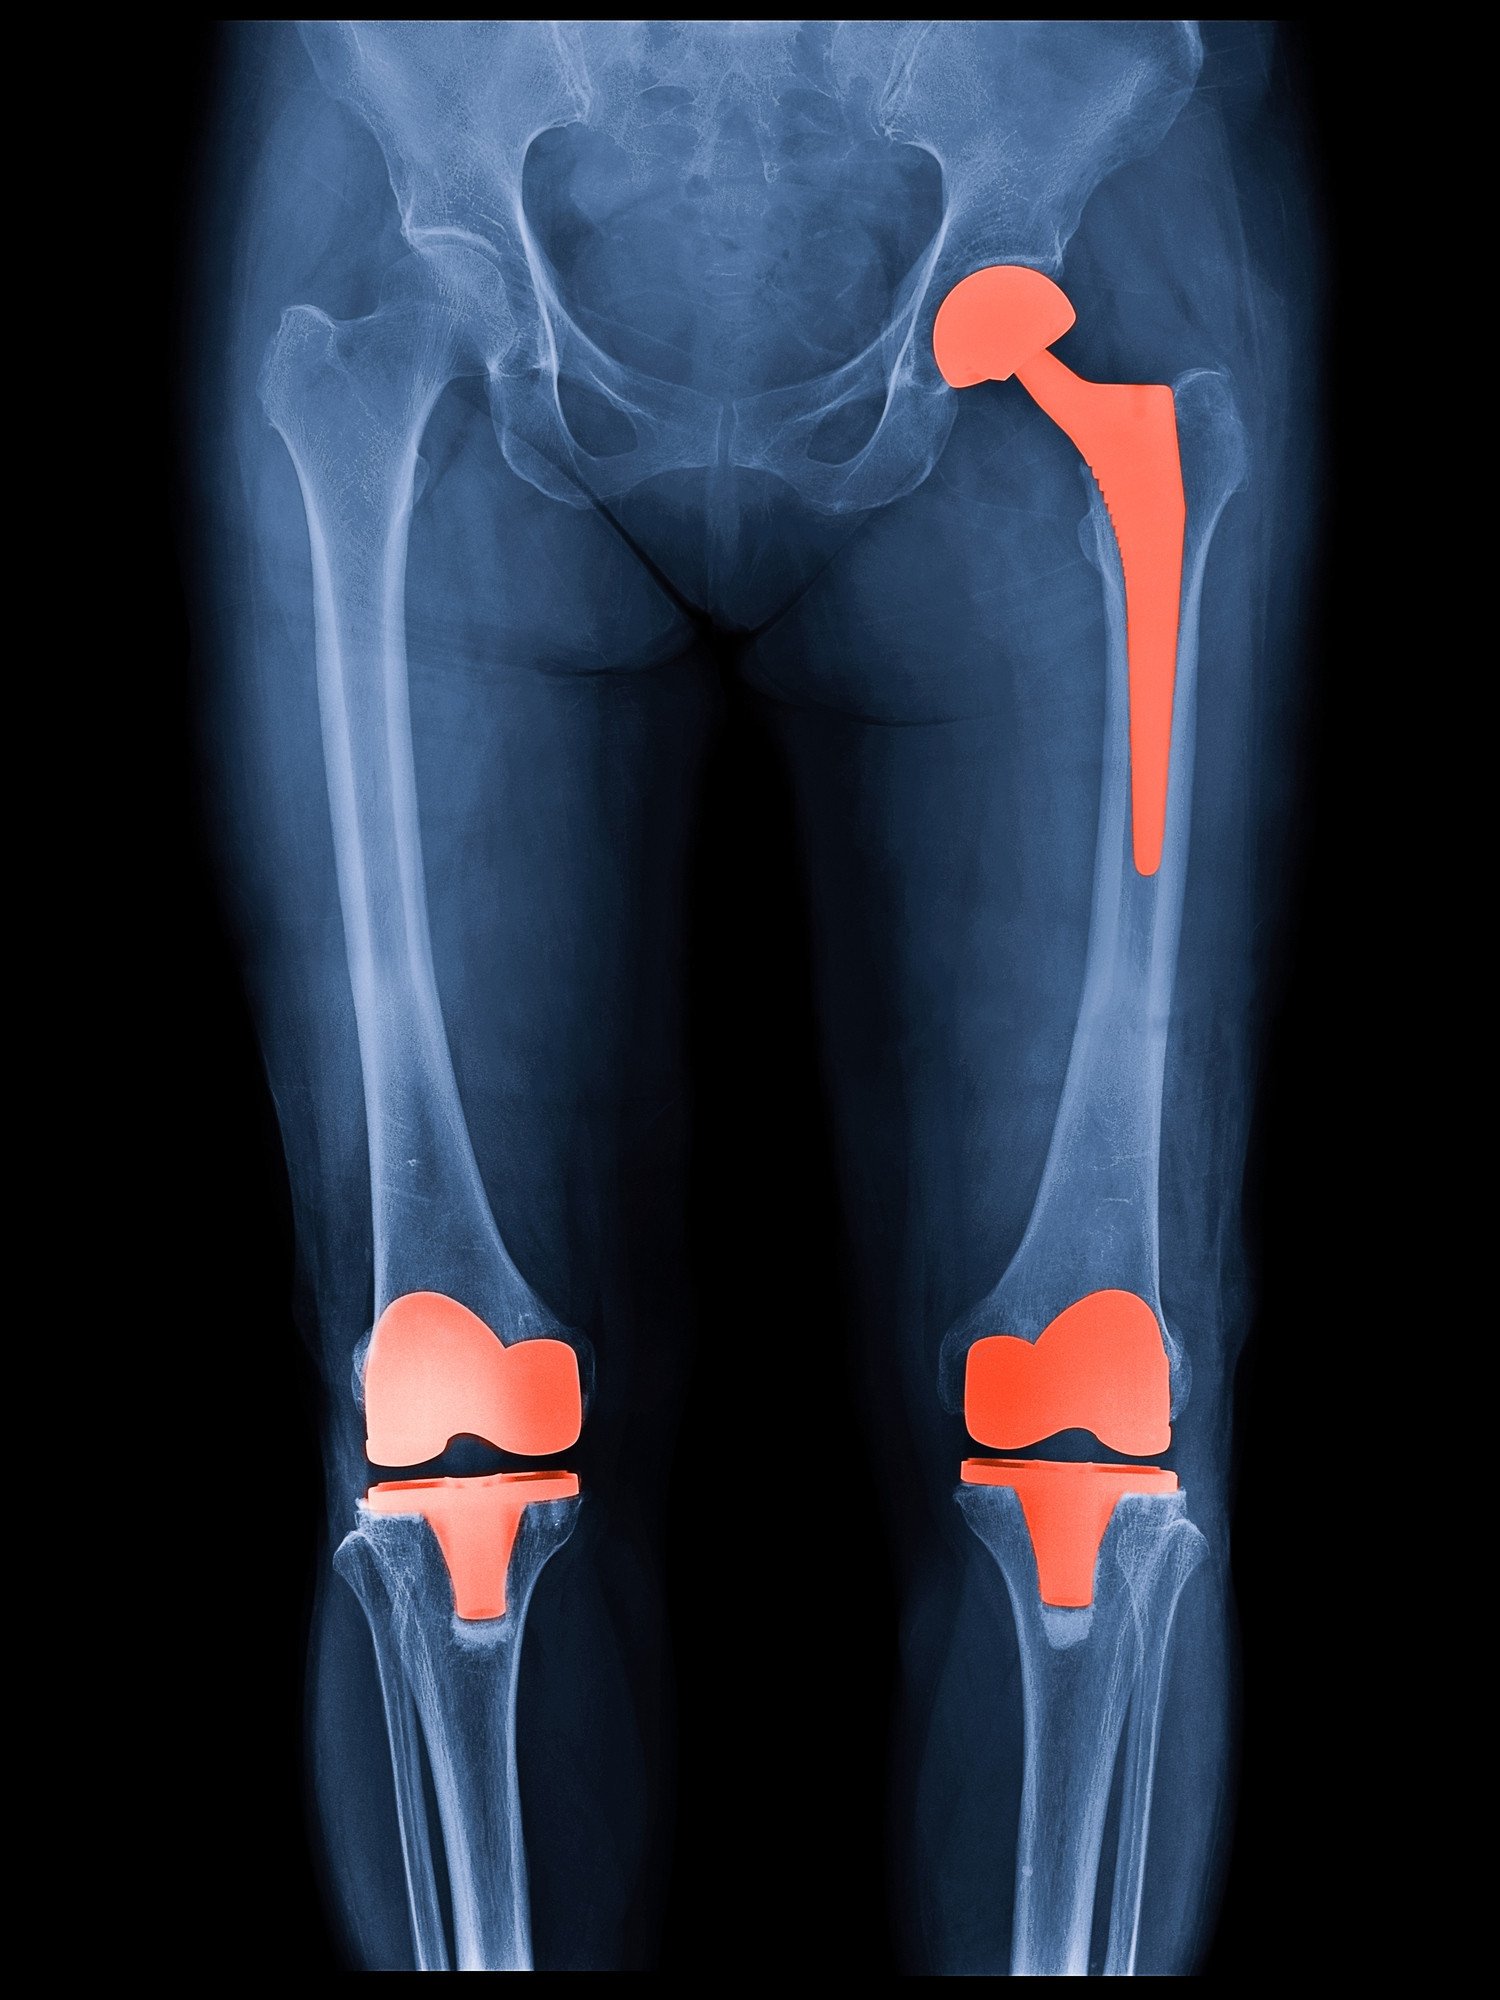

Knee replacement is one of the most frequently performed orthopedic surgeries. It is ideal for patients suffering from severe knee pain and limited mobility.

During the surgery, the damaged cartilage and bone are removed from the knee joint. Subsequently, the surgeon replaces them with metal and plastic components designed to replicate natural movement.

Hip replacement surgery is recommended for patients experiencing severe hip pain due to arthritis or injury.

In this procedure, the damaged hip joint is replaced with an artificial ball-and-socket implant. As a result, patients experience smoother and pain-free movement.